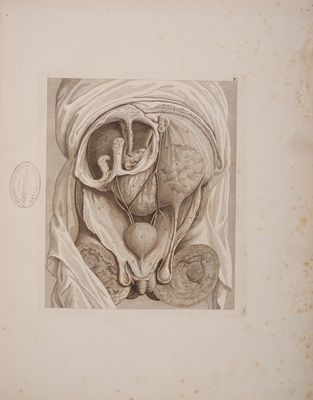

Tabulae Langenbeckii commentarium de structura peritonaei etc. spectantes / [Conrad Johann Martin Langenbeck].

- Konrad Johann Martin Langenbeck

- 1817

Credit: Tabulae Langenbeckii commentarium de structura peritonaei etc. spectantes / [Conrad Johann Martin Langenbeck]. Source: Wellcome Collection.